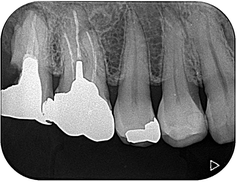

デンタル上で17根尖部から遠心にかけて透過像を認めました。歯冠遠心部はう蝕で崩壊しており、一見すると保存不可能に見える状態です。補綴物を撤去し、軟化象牙質を慎重に除去したところ、近心には十分な健全歯質が残存し、遠心にも健全歯質を保存することができました。レントゲンはあくまで画像であり、実際の状態と相違がある場合があります。レントゲンだけで判断する危険性を、改めて実感しました。

8か月後の経過観察になります。根尖部の透過像は大幅に縮小していることが確認できます。患者さんの自覚症状もなく、良好に経過しております。抜歯しなくて大丈夫だったことを大変喜ばれておりました。